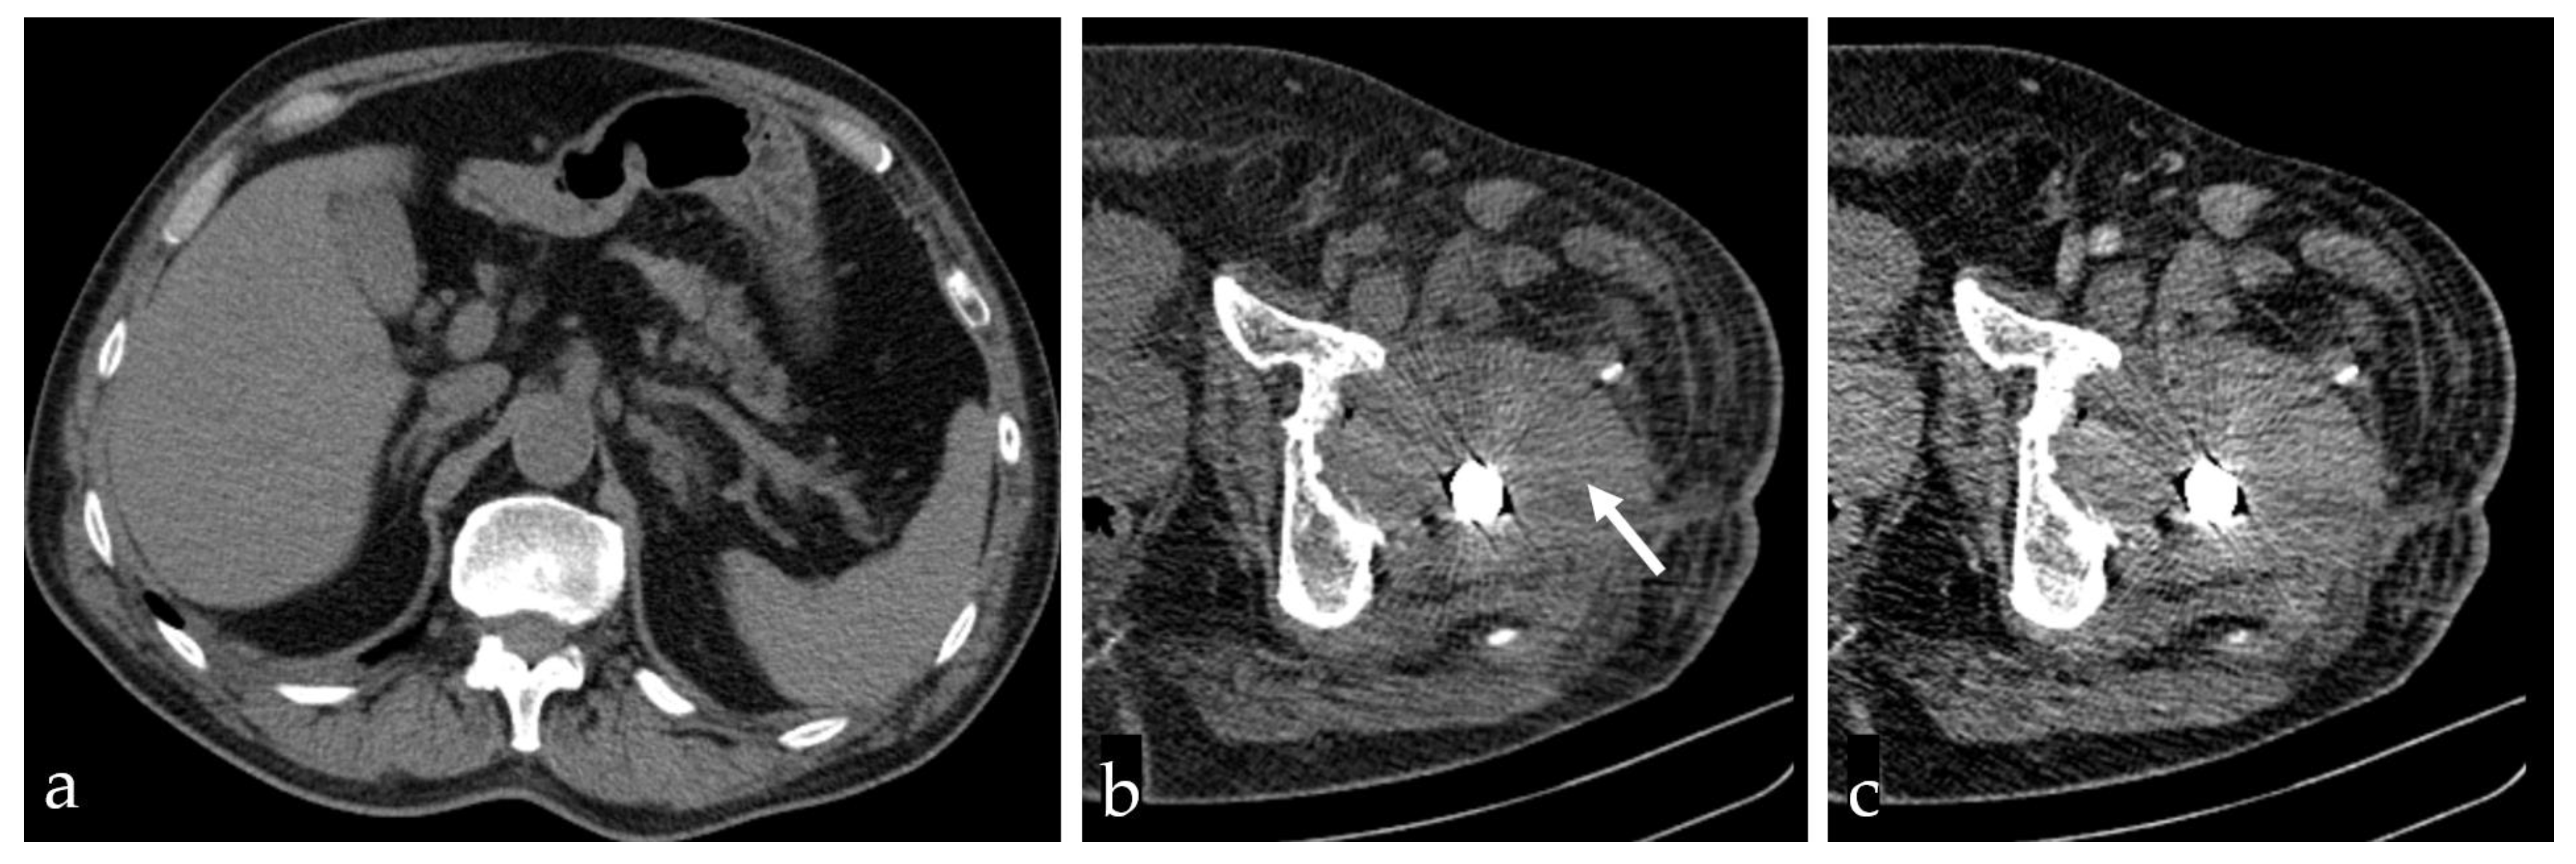

2. Case Presentation

2.1. Surgical Approach and Management

2.2. Surgical Technique and Management of Acetabular Component Revision